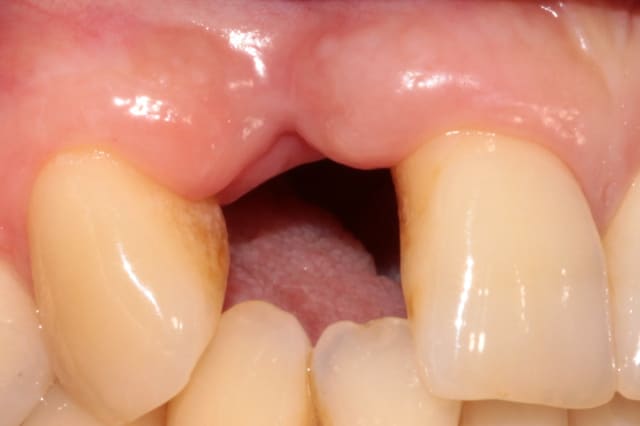

la suite 6 mois plus tard

photo 3 reconstruction avec le pilier en place

photo 4 vue occlusale de l'implant et de la reconstruction osseuse obtenue